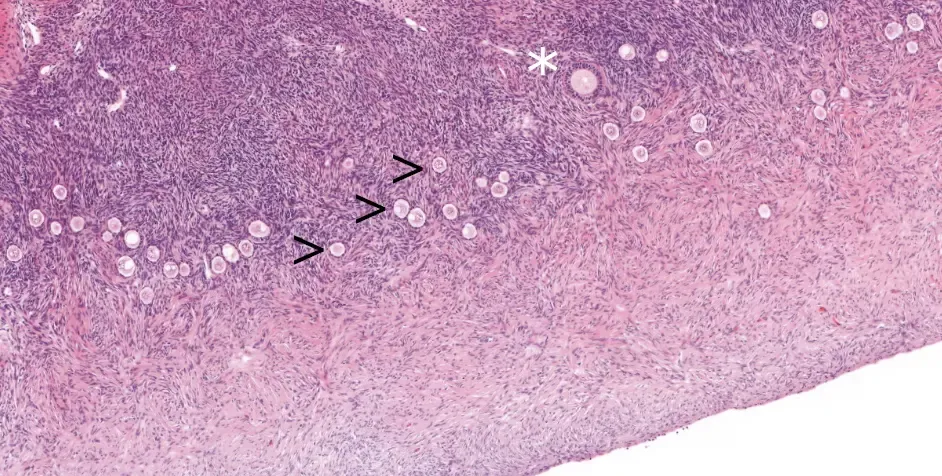

Reference standards for follicular density in ovarian cortex from birth to sexual maturity.

Hassan J, Knuus K, Lahtinen A, Rooda I, Otala M, Tuuri T, Gidlöf S, Edlund E, Menezes J, Malmros J, Byström P, Sundin M, Langenskiöld C, Vogt H, Frisk P, Petersen C, Damdimopoulou P, Jahnukainen K

Reprod Biomed Online 2023 Oct;47(4):103287

För att kunna studera hur miljöexponeringar och medicinska behandlingar påverkar äggstocken måste vi förstå dess funktion på en cellulär och molekylär nivå. Ett av våra forskningsmål är därför att identifiera olika celltyper inom äggstocken och studera hur dessa förändras genom livet. Äggstocken genomgår förändringar, t ex under puberteten, men påverkan på de minsta folliklarna, som innehåller omogna ägg, är inte väl undersökt. Vi analyserar äggstocksprover från flickor, unga tjejer och vuxna kvinnor för att skapa en omfattande bild av äggstockens utveckling och funktion från barndom, genom puberteten, till vuxen ålder.